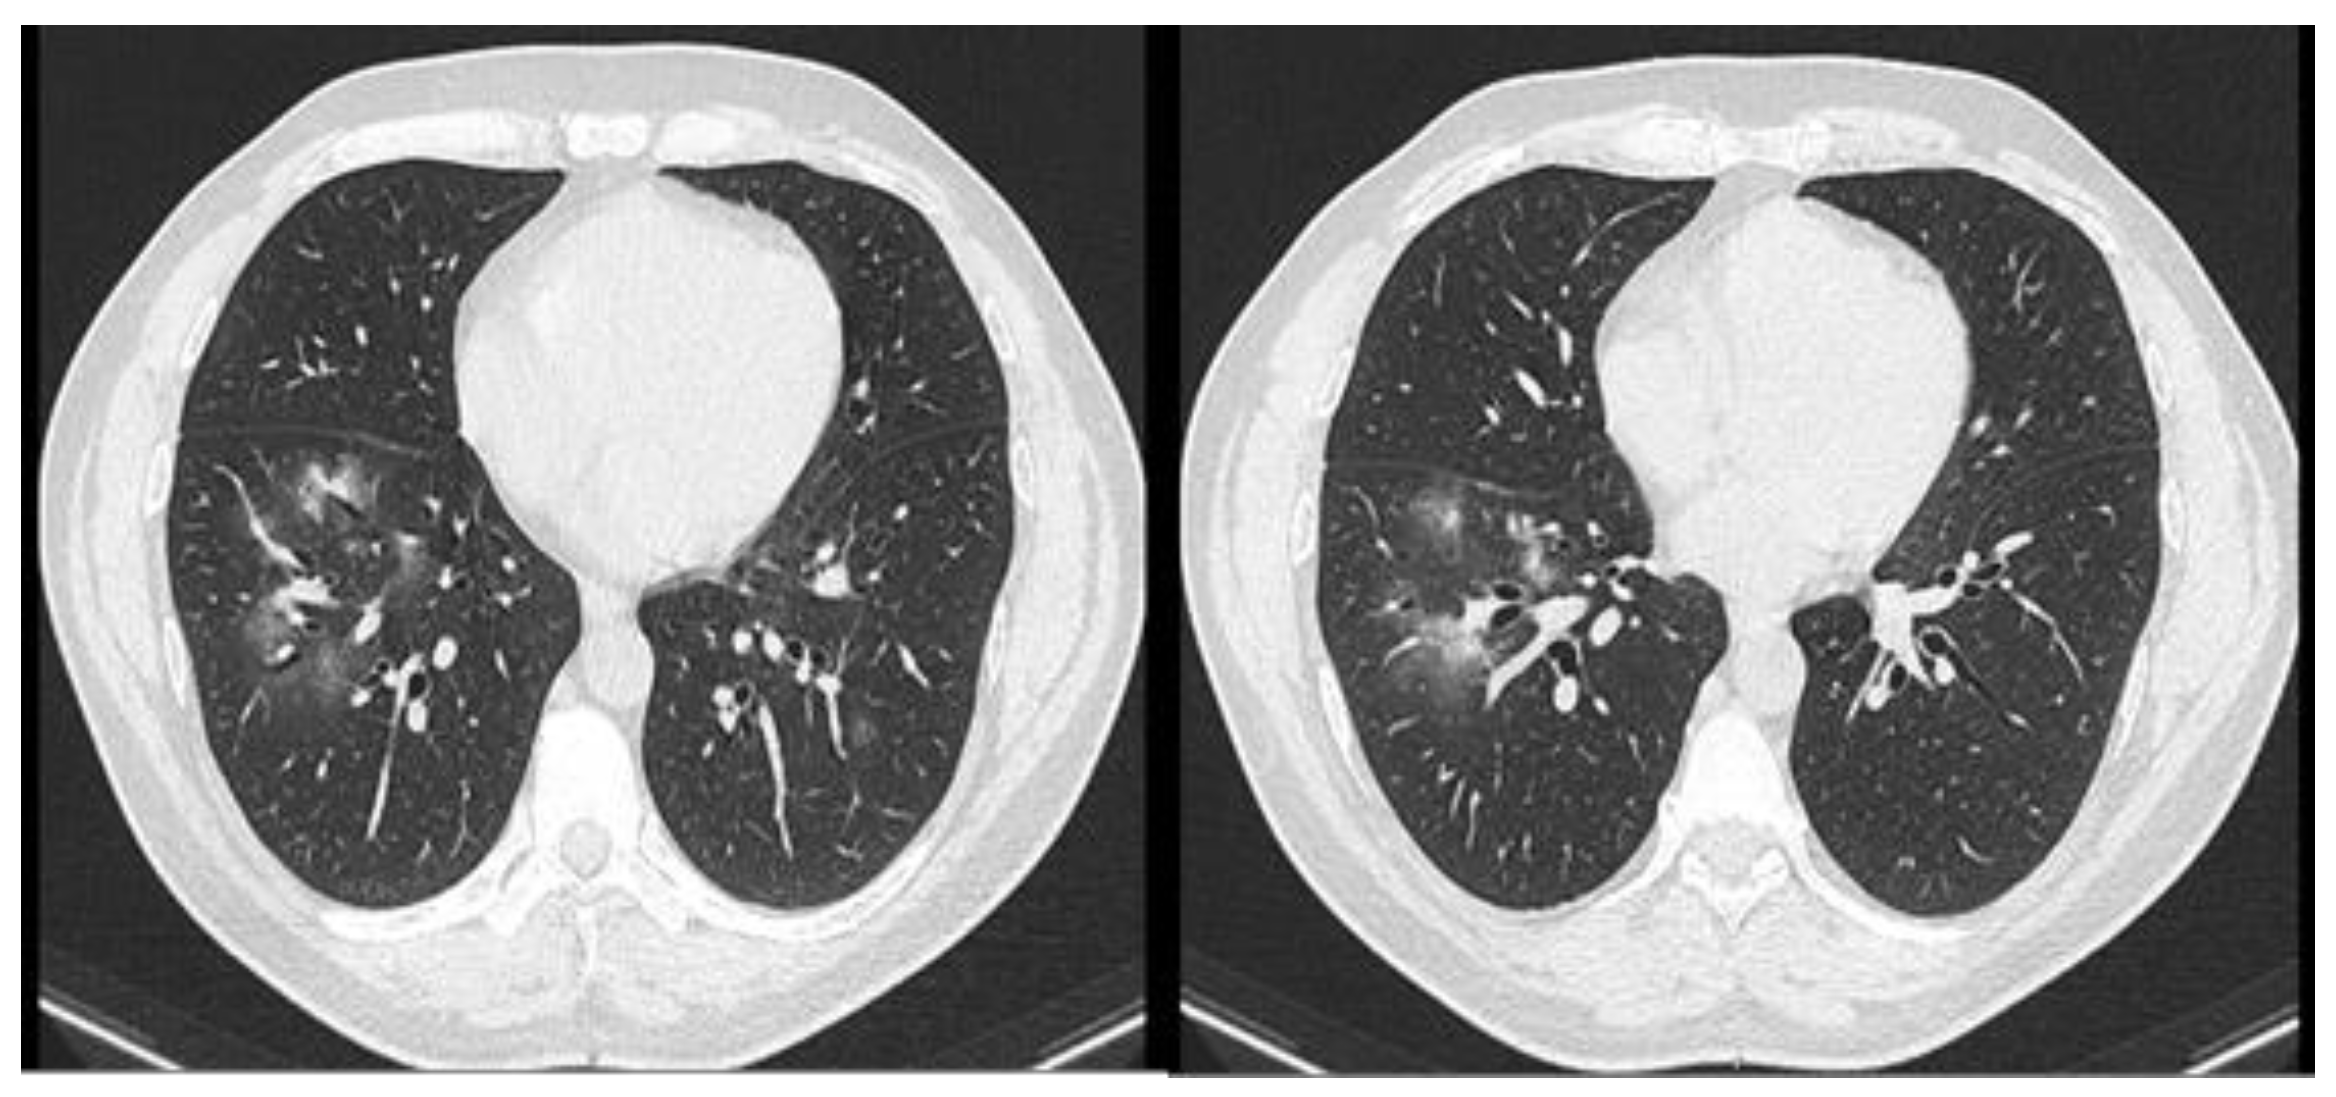

Case report